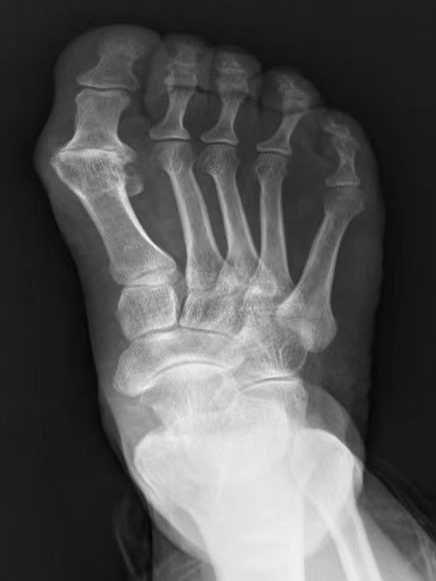

术前DR 术后DR

石阿姨入院后,创伤骨科主任房辉强高度重视,积极完善相关检查后立即组织科室成员进行讨论。结合石阿姨的症状和影像学表现,诊断为第一跖趾关节骨性关节炎(亦称拇僵硬)。结合最新的足踝外科领域进展,并与患者和家属进行充分沟通,决定为患者实施人工跖趾关节全关节置换术。

房辉强指出,随着生活质量的提高,人们对足踝部健康越来越重视。拇僵硬是以第一跖趾关节疼痛和活动受限为特征的关节退行性病变。早期症状主要包括疼痛、肿胀和跖趾关节滑膜炎,背伸受限则是其中最典型的特征之一。此类患者常诉步态僵硬,第一跖趾关节局部疼痛,在步行和站立时加重,休息后缓解。临床上常采用关节唇切除术、关节成形术、第一跖骨截骨术、跖趾关节融合术等,但这些传统术式在解决拇僵硬引起疼痛的同时,一定程度上牺牲了正常跖趾关节的功能活动。近年来,我国逐渐采用人工生物金属聚乙烯假体全关节置换术,很多足踝关节疾病在保守治疗无效的情况下均可采取小关节置换,此类手术创伤小、并发症少、既缓解疼痛又保留正常功能。